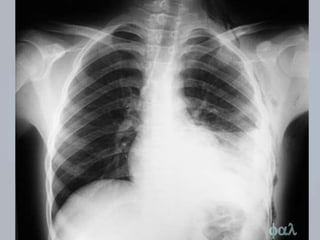

CONTUSÃO PULMONAR

 Laceração ou rompimento  mec. contusos ou

penetrantes;

 Sangue nos alvéolos e entre eles  dificuldade na

troca gasosa;

 Complicação comum e potencialmente letal;

 AVALIAÇÃO: os achados são variáveis; avalição

inicial pode não revelar dificuldade respiratória;

observar presença de retalho costal móvel.

 TRATAMENTO:

 Suporte ventilatório;

 Oximetria de pulso e capnografia;

 Reanimação volêmica  cautelosa ( edema) 

comprometimento da ventilação e a oxigenação.